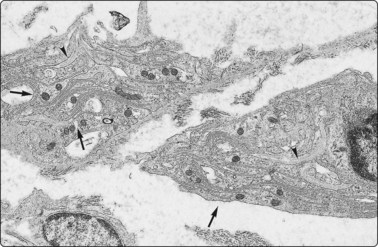

Electron microscopy32-38

Although immunocytochemistry has become the most important ancillary method for tumor subtyping, we still find EM necessary for some cases. EM is particularly useful in unusual lung or mediastinal lesions. In Silverman’s experience, FNB samples are the most frequent non-renal samples sent for EM.

We decide on cases to be further studied after an initial evaluation of material in the radiology theater. The most commonly used method of fixation is to eject the aspirate into a small test tube containing glutaraldehyde. Many methods of processing tissue are suggested, mainly with the aim of separating tumor tissue from contaminating red cells. We use Lazaro’s method of cell concentration. The small pellet produced by centrifugation is carefully removed and processed.39 For highly cellular aspirates, the material can be ejected as a semisolid droplet onto a carefully cleaned slide, which is then immersed in glutaraldehyde (compare cell ‘buttons’ as described above). The droplet can be processed on the slide or popped off for further handling. A report can be given in 24–48 hours if necessary.

There is evidence for representative sampling and superior fixation of FNB material compared with surgically excised material (Figs 2.20-2.22).24 In a review of 150 of our cases from various sites, 100 contained adequate well-preserved material for assessment. In 60% of these cases EM only confirmed the LM diagnosis, but in 40% the findings were diagnostic per se. The common applications of EM in FNAC are summarized in Table 2.3. In our experience, most value is obtained in recognizing neuroendocrine tumors and in the specific diagnosis of melanoma, mesothelioma and some carcinomas, including metastases, where immunocytochemistry often cannot provide such positive diagnostic features. An expanding literature about techniques and applications is available.

image

Fig. 2.20 Resin-embedded tissue fragment for EM

Fragment of sarcoma obtained with a standard 22-gauge needle, fixed in glutaraldehyde and processed on the slide, 1 µm section (Toluidin blue, HP).

Fig. 2.21 Electron microscopy – carcinoid tumor

FNB of metastatic neoplasm in the liver. Numerous intracytoplasmic rounded neurosecretory granules averaging 155 nm in diameter. In some, a submembranous lucent halo is seen (arrows) (EM × 13 650).

Fig. 2.22 Electron microscopy – schwannoma

Screw needle biopsy (Rotex II) of an atypical soft tissue tumor in the neck of a 20-year-old man. The complex intertwining cytoplasmic processes (arrows) and the associated external (basal) lamina (arrowheads) indicate schwannian differentiation. The abundance of the lucent proteoglycan-containing extracellular matrix is in keeping with Antoni B tissue (EM × 9940).